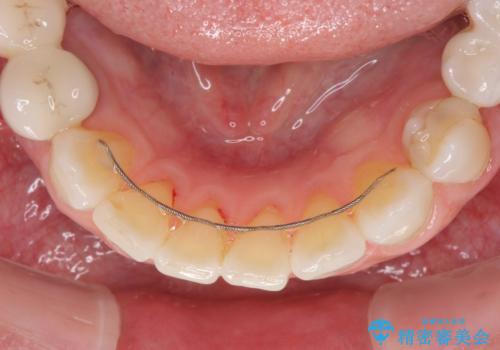

外科処置を行うため、治癒を待つ期間が数ヶ月あるため、その期間を利用して下顎前歯のスペースを矯正治療で閉じることとしました。

矯正治療までは考えていなかったそうですが、物が挟まっていた前歯のスペースがなくなり、矯正治療を行って良かったとのことでした。